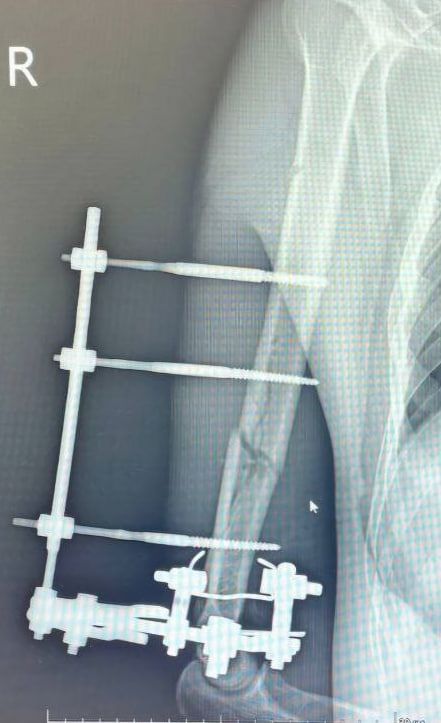

Пациент поступил в Истринскую больницу с частичной ампутацией руки. Об этом сообщает областной Минздрав.

При поступлении в стационар рука держалась только на мягких тканях.

«Изначально были риски потери руки, но нам удалось ее спасти. Мы провели хирургическую обработку, зафиксировали конечность в правильном положении. Затем выполнили остеосинтез аппаратом Илизарова», – рассказал заведующий травматологическим отделением Роберт Миллер.

Пациент провел в отделении полтора месяца. Сейчас он выписан, находится под наблюдением травматолога, проходит реабилитацию у невролога, занимается лечебной физкультурой для восстановления функций травмированной руки.